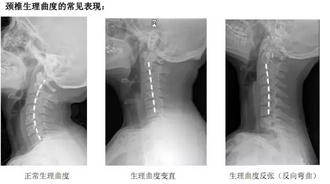

请问一下专家,颈椎病生理曲直度是多少呢? ask150634 2009-07-27 15:20 投诉 名医在 在各个颈椎推体后缘连续的一条光滑的弧形曲线,称之为颈椎生理曲线,正常值为12士5m

颈椎生理曲线变直又称为一字型颈部或乌龟